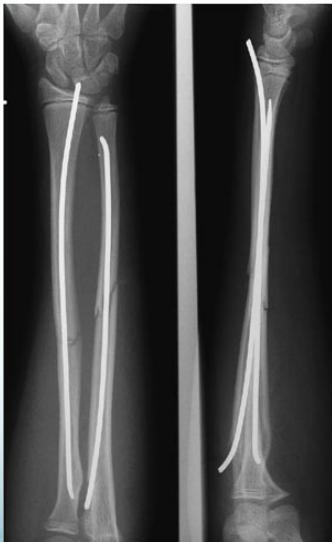

Elastic Intramedullary Nails

- For unstable fractures – minimal surgery

- Put back slab for 2 weeks only